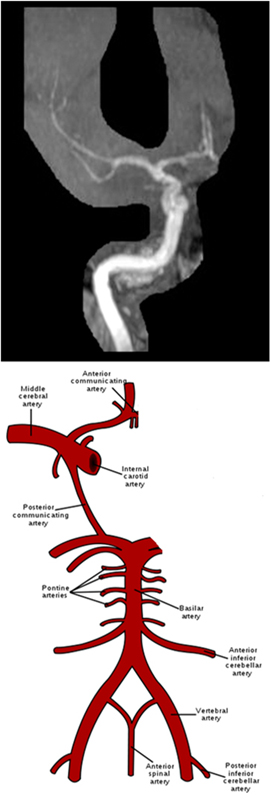

Series Name = “COW”/”Right”/”Left”/”Basilar” whichever you are working on

MRA Brain WO Protocol Image4

MRA Brain WO Protocol Image6